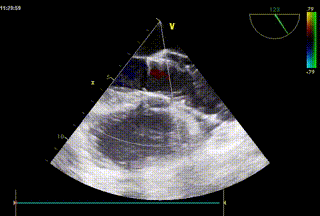

男性,86岁。入院7年余无明显诱因出现活动后胸闷伴气促,反复因“心衰”就诊当地医院,1月前上述症状加重。心脏超声提示:左室向心性肥大伴左室整体收缩功能减退,主动脉瓣钙化伴关闭不全(中-重度反流),心包积液(少量),三尖瓣轻度反流,二尖瓣未见明显反流,肺动脉瓣轻度反流。

术后超声评估:

超声结合长轴短轴评估,无明显反流,瓣膜工作状态良好